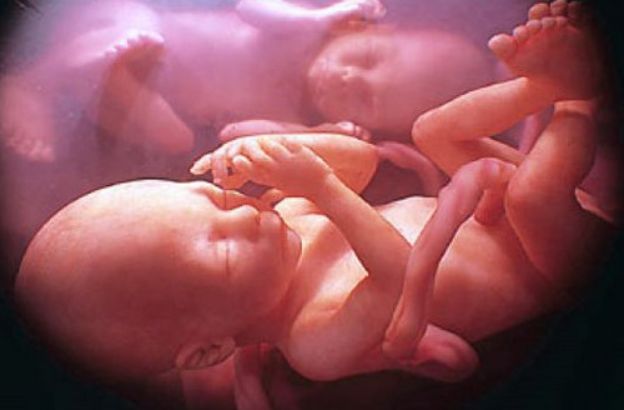

L’interazione sociale comincia nel feto: il caso dei gemelli ripresi con l’ultrasonografia

I ricercatori hanno osservato i feti utilizzando un particolare tipo di tecnica medica chiamata ultrasonografia a quattro dimensioni, attraverso la quale è possibile ottenere immagini tridimensionali ricostruite in sequenza temporale.

Le analisi sulle coppie di gemelli sono avvenute alla quattordicesima e alla diciottesima settimana di gestazione e, in entrambi i periodi, i ricercatori hanno riscontrato nei fratelli, alcuni movimenti volontari e rivolti l'uno nei confronti dell'altro.

I gemelli, già a partire dalla quattordicesima settimane e con una decisa intensificazione durante la diciottesima, si cercano l’un l’altro con movimenti intenzionali e utilizzano il suddetto movimento quasi per coccolarsi.